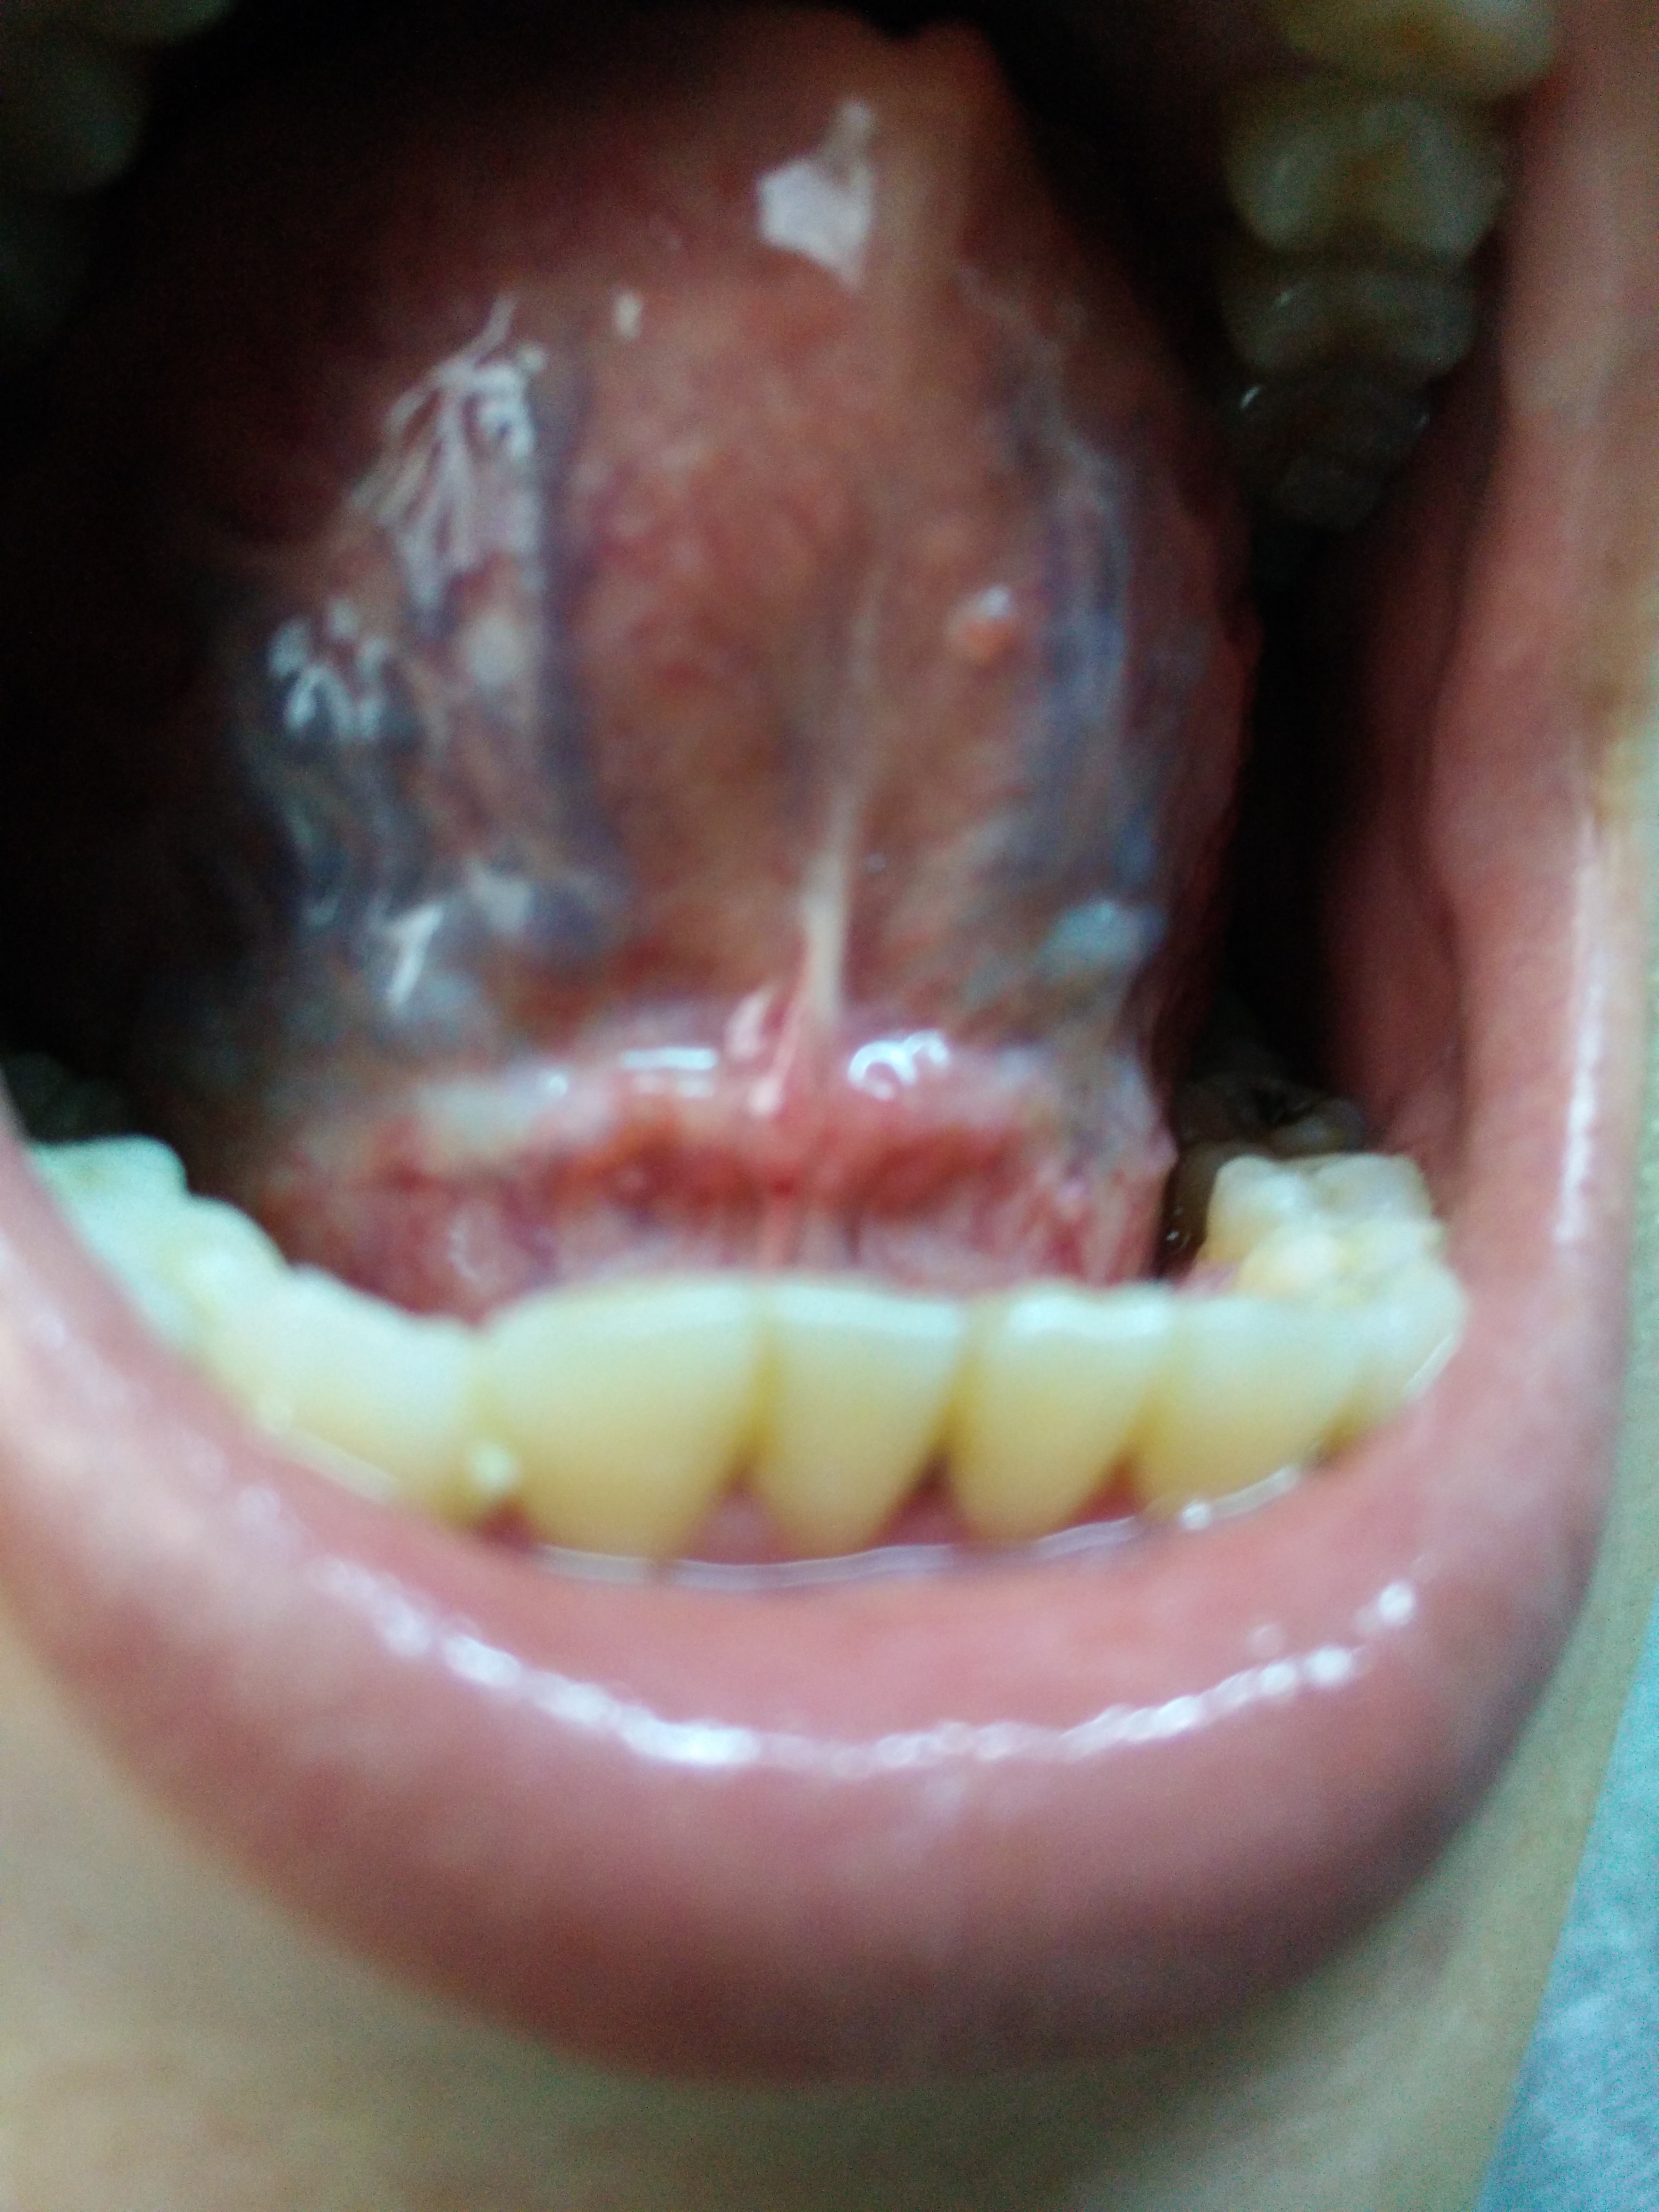

衣 衣袖 惊鸿一瞥 正式会员 注册 2015/04/09 帖子 46 获得点赞 0 声望 0 2015/04/24 #62 中医那些事 说: 舌胖,满舌黄腻苔。此为脾虚痰盛,郁久化热且夹风。 治应祛痰瘀,散风 疏风,健脾养肝滋肾。 非一个方 点击展开... 舌苔有点黄,照片拍出来不明显 饭前: 饭后: 人感觉精神好多了,下午没那么困了。 心口以上觉得挺轻松的,但是觉得腹重,大便不畅,小便尚可。早上醒来没那么口渴了。 20日刚来例假,提前了5天,小腹左边感觉凉凉的隐痛。一般7天干净,从昨天开始量少,色淡 麻烦医生再给我看看 附件 饭前.jpg 2.4 MB 查看: 58 饭后.jpg 2.3 MB 查看: 46 饭后2.jpg 2.3 MB 查看: 48

中医那些事 说: 舌胖,满舌黄腻苔。此为脾虚痰盛,郁久化热且夹风。 治应祛痰瘀,散风 疏风,健脾养肝滋肾。 非一个方 点击展开... 舌苔有点黄,照片拍出来不明显 饭前: 饭后: 人感觉精神好多了,下午没那么困了。 心口以上觉得挺轻松的,但是觉得腹重,大便不畅,小便尚可。早上醒来没那么口渴了。 20日刚来例假,提前了5天,小腹左边感觉凉凉的隐痛。一般7天干净,从昨天开始量少,色淡 麻烦医生再给我看看

衣 衣袖 惊鸿一瞥 正式会员 注册 2015/04/09 帖子 46 获得点赞 0 声望 0 2015/04/30 #64 中医那些事 说: 发个舌图看看。 愚见,还是先祛痰瘀,再养肝肾。再加些祛风疏风的药。风行数变且与痰结,则症状千变万化, 点击展开... 请医生再帮我看看 。 附件 舌照.png 210.9 KB 查看: 57 舌照2.png 235.8 KB 查看: 71 舌照3.png 226.9 KB 查看: 69

衣 衣袖 惊鸿一瞥 正式会员 注册 2015/04/09 帖子 46 获得点赞 0 声望 0 2015/05/06 #65 中医那些事 说: 舌胖,满舌黄腻苔。此为脾虚痰盛,郁久化热且夹风。 治应祛痰瘀,散风 疏风,健脾养肝滋肾。 非一个方 点击展开... 附件 IMG20150506175501.jpg 2.7 MB 查看: 59 IMG20150506175532.jpg 2.7 MB 查看: 55 IMG20150506180037.jpg 2.7 MB 查看: 50 IMG20150506180133.jpg 2.9 MB 查看: 58 舌照1.png 216.5 KB 查看: 55

衣 衣袖 惊鸿一瞥 正式会员 注册 2015/04/09 帖子 46 获得点赞 0 声望 0 2015/05/11 #74 本帖最后由 衣袖 于 2015-5-11 09:06 编辑 中医那些事 说: 肝滋肾。 非一个方 点击展开... 早饭前有点淡黄: 早饭后黄不明显了: 附件 IMG20150511073416.jpg 2.4 MB 查看: 44 IMG20150511073421.jpg 2.4 MB 查看: 51 IMG20150511085654.jpg 2.2 MB 查看: 54 IMG20150511085707.jpg 2.2 MB 查看: 55

衣 衣袖 惊鸿一瞥 正式会员 注册 2015/04/09 帖子 46 获得点赞 0 声望 0 2015/05/17 #75 中医那些事 说: 舌胖,满舌黄腻苔。此为脾虚痰盛,郁久化热且夹风。 治应祛痰瘀,散风 疏风,健脾养肝滋肾。 非一个方 点击展开... 舌苔还是有点黄,照片看不出来: 附件 IMG20150517064834.jpg 2.3 MB 查看: 54 IMG20150517064902.jpg 2.1 MB 查看: 48 IMG20150517064909.jpg 2.1 MB 查看: 51

衣 衣袖 惊鸿一瞥 正式会员 注册 2015/04/09 帖子 46 获得点赞 0 声望 0 2015/05/22 #76 中医那些事 说: 舌胖,满舌黄腻苔。此为脾虚痰盛,郁久化热且夹风。 治应祛痰瘀,散风 疏风,健脾养肝滋肾。 非一个方 点击展开... 今早的: 附件 IMG20150522075355.jpg 2.7 MB 查看: 52 IMG20150522075400.jpg 2.3 MB 查看: 49

衣 衣袖 惊鸿一瞥 正式会员 注册 2015/04/09 帖子 46 获得点赞 0 声望 0 2015/05/27 #77 中医那些事 说: 舌胖,满舌黄腻苔。此为脾虚痰盛,郁久化热且夹风。 治应祛痰瘀,散风 疏风,健脾养肝滋肾。 非一个方 点击展开... 饭前的,舌苔薄黄: 附件 IMG20150527082719.jpg 2 MB 查看: 47 IMG20150527082724.jpg 2.1 MB 查看: 48 IMG20150527082733.jpg 1.9 MB 查看: 44

衣 衣袖 惊鸿一瞥 正式会员 注册 2015/04/09 帖子 46 获得点赞 0 声望 0 2015/06/01 #78 中医那些事 说: 舌胖,满舌黄腻苔。此为脾虚痰盛,郁久化热且夹风。 治应祛痰瘀,散风 疏风,健脾养肝滋肾。 非一个方 点击展开... 附件 IMG20150601083145.jpg 2.3 MB 查看: 45 IMG20150601083206.jpg 2.3 MB 查看: 46